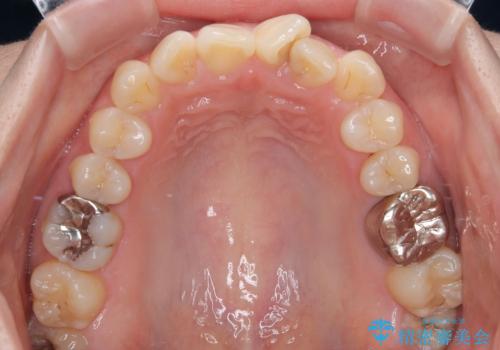

診察の結果、上下の前歯部に**叢生(そうせい/歯のガタガタ・重なり)**が認められました。

特に上の前歯にはねじれや重なりがあり、審美的にも清掃性にも影響している状態でした。

また、上顎前歯の重なっていた部分にはむし歯が見つかり、治療中に適切な処置を行っています。